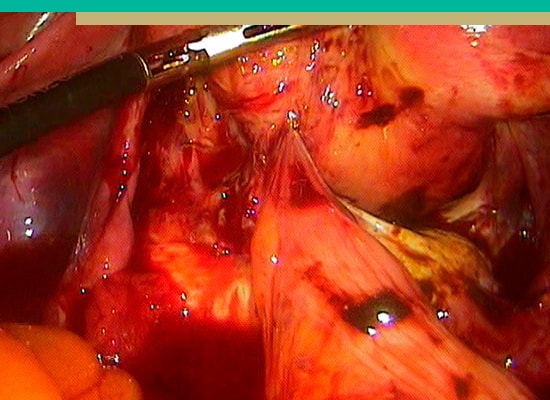

- Cirugía Laparoscópica Diagnóstica y de Tratamiento